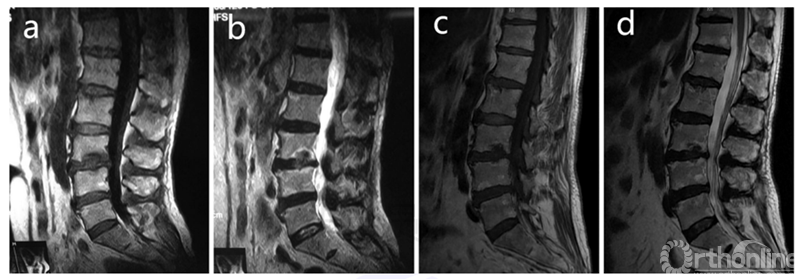

(2)椎间盘封闭术

近期,赵凤东教授发表了关于保守治疗无效的疼痛性许莫氏结节的治疗方式文章。赵凤东教授团队对46例疑似来自于疼痛性许莫氏结节的慢性腰痛患者进行椎间盘造影和椎间盘内封闭治疗(注射1ml倍他米松与罗哌卡因1:1的混合液),结果发现89.2%患者的ODI和腰痛VAS评分明显提高,无加重的患者,随访1年,仍保持良好的效果。他们也发现疼痛性许莫氏结节周围的椎体骨髓在MRI上特征性的信号是:低T1和高T2信号。而在治疗后随访12个月,其信号转变为高T1和T2信号或低T1和T2信号。但许莫氏结节的大小不随时间变化。